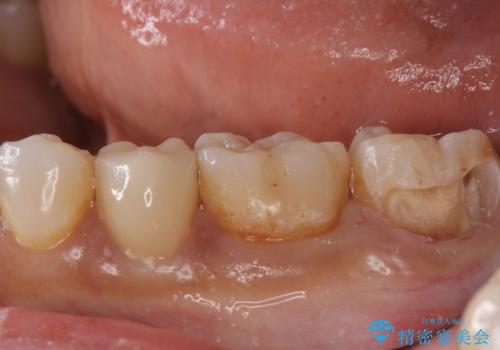

- 出産して落ち着いたから虫歯のチェックをしてほしいとのことで来院されました。

左下の奥歯に詰まっている樹脂の周辺が虫歯になっていたため、治療を進めていくこととなしました。

今回の場合、虫歯の大きさが大きく本来であれば歯茎に対しても治療をすることが検討されケースですが、ご希望されなかったため被せ物のみでの治療となりました。